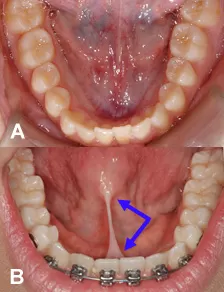

So sánh : A thắng lưỡi bình thường và B thắng lưỡi ngắn bám vào mặt sau răng cửa giữa hàm dưới và mặt dưới chóp lưỡi